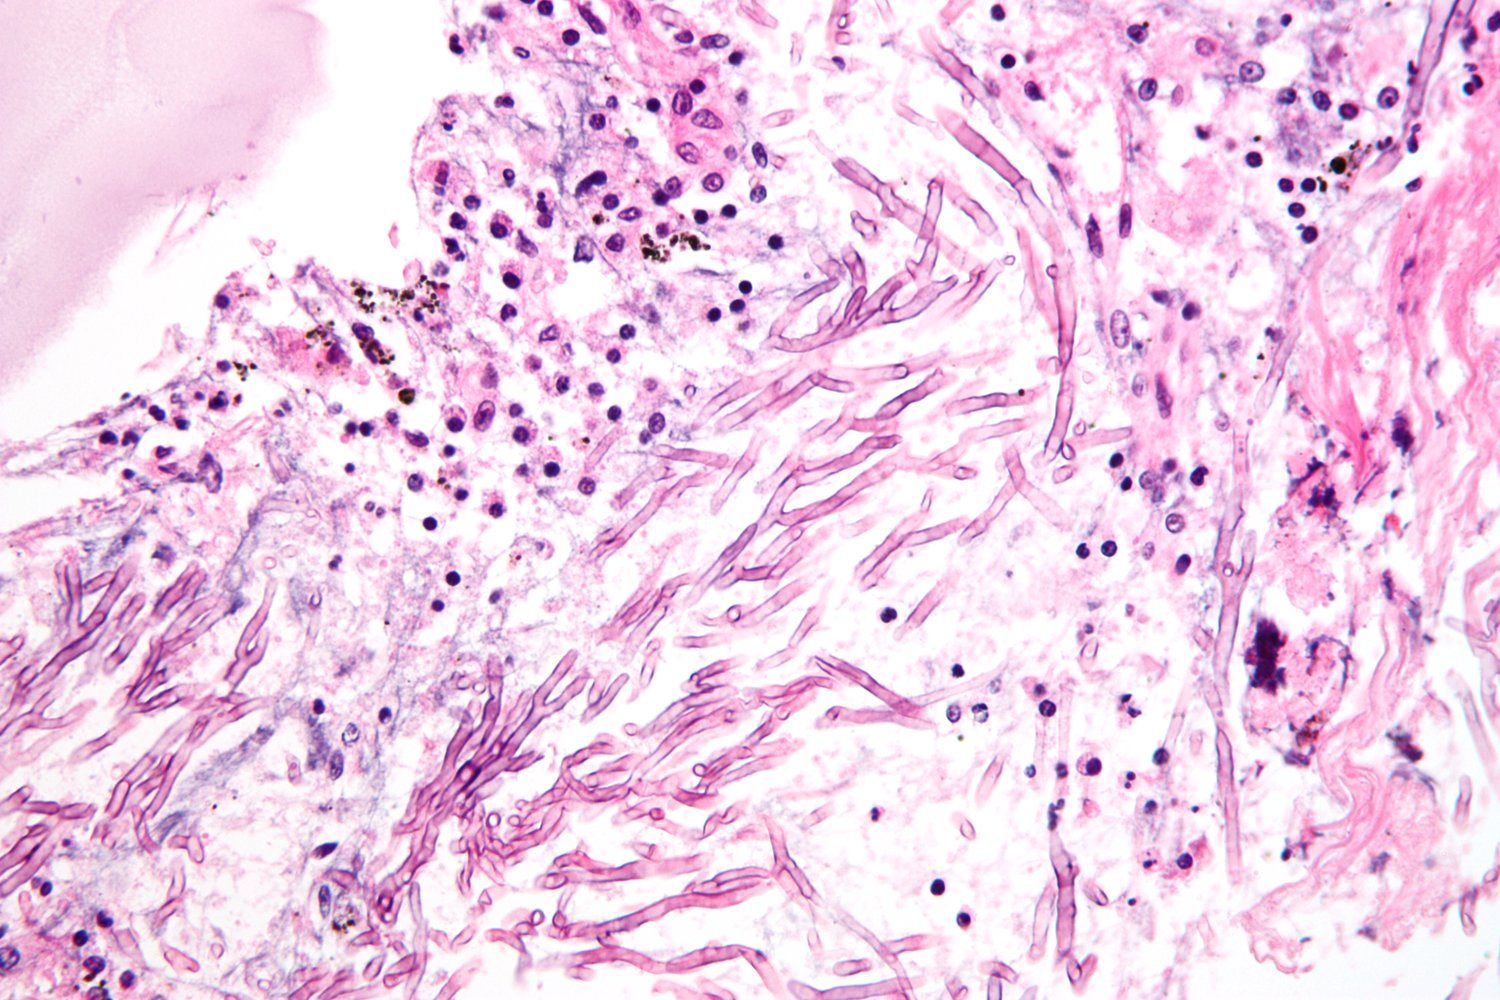

Diagnostic confirmation [4]

• Obtain a tissue or fluid sample (e.g., via bronchoscopy with biopsy and/or bronchoalveolar lavage) if invasive aspergillosis is supported by laboratory and imaging findings. [8]

• Send samples for culture and cytology.

• Staining: Gomori methenamine silver stain or periodic acid-Schiff stain

• Findings: monomorphic and/or septate hyphae branchingdichotomously at 45°

Positive culture or biopsy showing septate hyphae is the gold standard for the diagnosis of invasive aspergillosis.